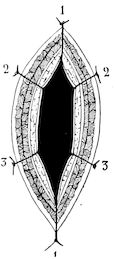

| Herniæ | 741 | |||

| Inguinal hernia in young pigs | 741 | |||

| Imperforate anus | 742 | |||

| Prolapsus and inversion of the rectum | 743 | |||